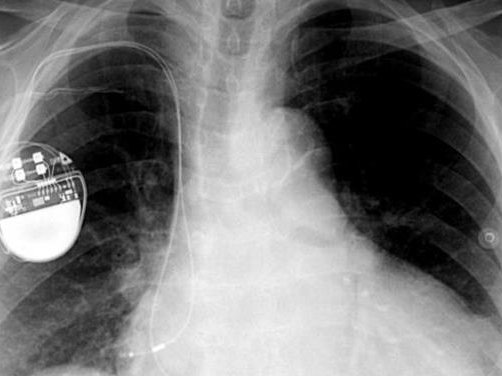

Ο πρώην αντιπρόεδρος των ΗΠΑ, Ντικ Τσένι, ζήτησε από τους γιατρούς του να απενεργοποιήσουν τη λειτουργία ασύρματης δικτύωσης στον βηματοδότη που επρόκειτο να του εμφυτεύσουν.

Ο λόγος για τον πρώην αντιπρόεδρο των ΗΠΑ, Ντικ Τσένι, ο οποίος ζήτησε από τους γιατρούς του να απενεργοποιήσουν τη λειτουργία ασύρματης δικτύωσης στον βηματοδότη που επρόκειτο να του εμφυτεύσουν.

Ο Ντικ Τσένι φοβόταν για επιθέσεις χάκερ στην καρδιά του -και δεν είναι ο μόνος που ανησυχεί.

Ο Τσένι, ο οποίος είχε υποστεί αλλεπάλληλα εμφράγματα, υποβλήθηκε στην επέμβαση το 2007. Αποκάλυψε τι είχε συμβεί το 2013 σε συνέντευξή του στο δίκτυο CBS. «Είχα επίγνωση του κινδύνου που υπήρχε» είχε πει τότε.

Όπως επισημαίνει τώρα ο δικτυακός τόπος του περιοδικού Science, ειδικοί σε θέματα ασφάλειας υπολογιστών έχουν αποδείξει εδώ και καιρό ότι είναι δυνατό να παρέμβει κανείς σε εμφυτεύσιμες συσκευές όπως οι βηματοδότες, οι απινιδωτές και οι αντλίες ινσουλίνης.

Πολλά από τα σύγχρονα μοντέλα μπορούν να ρυθμιστούν αν χρειαστεί μέσω ενός φορητού ελεγκτή που συνδέεται με τη συσκευή μέσω Bluetooth. Υπάρχουν όμως και συσκευές που συνδέονται απευθείας στο Διαδίκτυο μέσω WiFi, και είναι δυνητικά πιο ευπαθείς σε επιθέσεις.